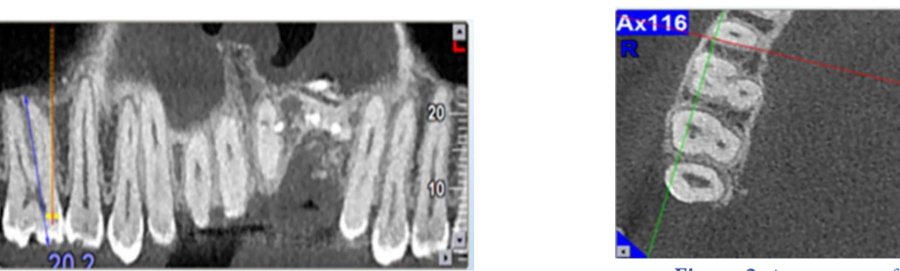

Root Canal Morphology of Maxillary Second Molars according to Age and Gender in a Selected Iranian Population: A Cone-Beam Computed Tomography Evaluation